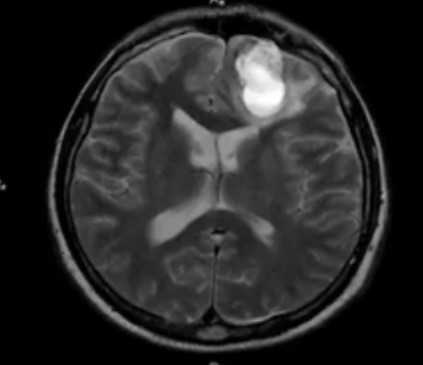

- Опухоли и подозрение на опухоли.

МРТ височных костей позволяет выявить такие заболевания, как острые и хронические отиты, воспаления внутреннего уха, опухоли доброкачественного и злокачественного характера, травмы и переломы височных костей, наличие инфекционного процесса в данной области, отосклероз и другие дегенеративные патологии.

В тех случаях, когда есть подозрение на наличие опухоли, или необходимо уточнить более четко границы патологии, может быть назначена МРТ с контрастированием. Контраст вводится внутривенно после проведения бесконтрастного сканирования строго по показаниям. Распространяясь с кровотоком и накапливаясь в пораженных тканях, контрастное вещество способствует лучшей визуализации проблемных участков, позволяет косвенно судить о злокачественности опухоли, ее структуре. Контрастное вещество представляет собой препарат на основе редкоземельного металла гадолиния, который не наносит вреда организму и полностью выводится в течение суток естественным путем.